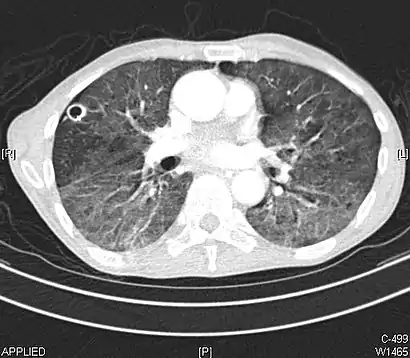

CT showing diffuse ground-glass opacities in periphery of both lungs in patient with COVID-19.

Ground-glass opacity is among the most common imaging findings in patients with confirmed COVID-19.[17][18] One systematic review found that among patients with COVID-19 and abnormal lung findings on CT, greater than 80% had GGOs, with greater than 50% having mixed GGOs and consolidation.[17] GGOs with mixed consolidation has most often been found in elderly populations.[19] Several studies have described a pattern among initial, intermediate, and hospital discharge imaging findings in the disease course of COVID-19. Most commonly, initial CT imaging reveals bilateral GGOs at the periphery of the lungs. During initial stages, this is most often found in the lower lobes, although involvement of the upper lobes and right middle lobe has also been reported early in the disease course.[17][19] This is in contrast to the two similar coronaviruses, SARS and MERS, which more commonly involve only one lung on initial imaging.[20][21] As the COVID-19 infection progresses, GGOs typically become more diffuse and often progress to consolidation.[12][19] This is sometimes accompanied by the development of a crazy paving pattern and interlobular septal thickening.[19] In many cases the most severe pulmonary CT abnormalities occurred within 2 weeks after symptoms began.[18] At this point, many individuals begin showing resolution of consolidation and GGOs as symptoms improve. However, some patients have worsening symptoms and imaging findings, with further increase in septal thickening, GGOs, and consolidation. These patients may develop lung "white-out" with progression to acute respiratory distress syndrome (ARDS) requiring treatment escalation.[18][22]

Preliminary reports have shown many patients have residual GGOs at time of discharge from the hospital. Due to the novelty of COVID-19, large studies investigating the long-term pulmonary CT changes have yet to be completed. However, long-term pulmonary changes have been seen in patients after recovery from SARS and MERS, suggesting the possibility of similar long-term complications in patients who have recovered from acute COVID-19 infection.[23]